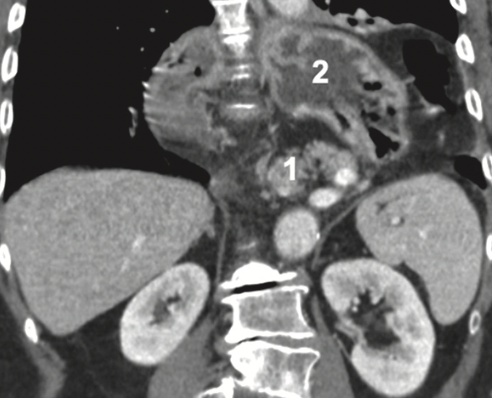

Discusión: Las hernias hiatales paraesofágicas tipo IV suelen contener todo el estómago, colon transverso, epiplón, a veces intestino delgado y más raro el bazo. En la hernia hiatal masiva (HHM) a los órganos señalados se suman el duodeno, la vía biliar y el páncreas. La HHM es de rara ocurrencia y constituye un desafío quirúrgico. La literatura reporta algo más de una treintena de casos en los últimos 50 años casos, no todos operados. El manejo debe ser quirúrgico y precoz, a fin de restaurar prontamente la anatomía y realizado por un equipo con experiencia en el manejo de hernias hiatales complejas.